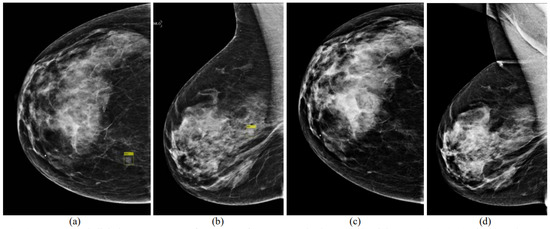

5.1. Detection of Breast Masses